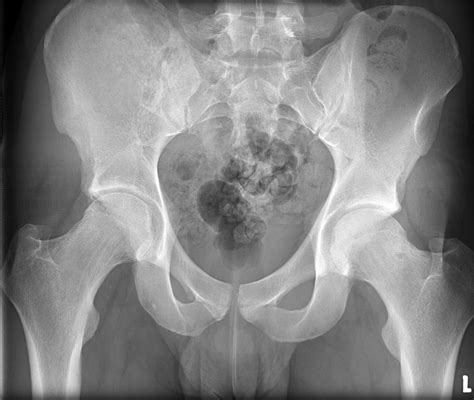

Interpreting a Normal Hip X Ray

Interpreting a Normal Hip X Ray requires a trained eye. Radiologists look for specific features to determine the health of the hip joint. Key elements include:

• Bone Density: The density and structure of the bones should appear uniform and without any fractures or lesions.

• Joint Space: The space between the femoral head and the acetabulum should be consistent and without narrowing, which could indicate arthritis.

• Alignment: The femoral head should be properly seated within the acetabulum, and the neck of the femur should align correctly with the shaft.

• Soft Tissues: The surrounding soft tissues should appear normal, without any swelling or abnormalities.

Common Conditions Detected by a Hip X Ray

A Normal Hip X Ray helps in identifying various conditions. Some of the most common include:

• Fractures: Visible breaks in the bone structure.

• Dislocations: Misalignment of the femoral head within the acetabulum.

• Arthritis: Narrowing of the joint space and bone spurs.

• Developmental Dysplasia: Abnormal development of the hip joint, often seen in infants and children.

• Osteonecrosis: Death of bone tissue due to lack of blood supply.